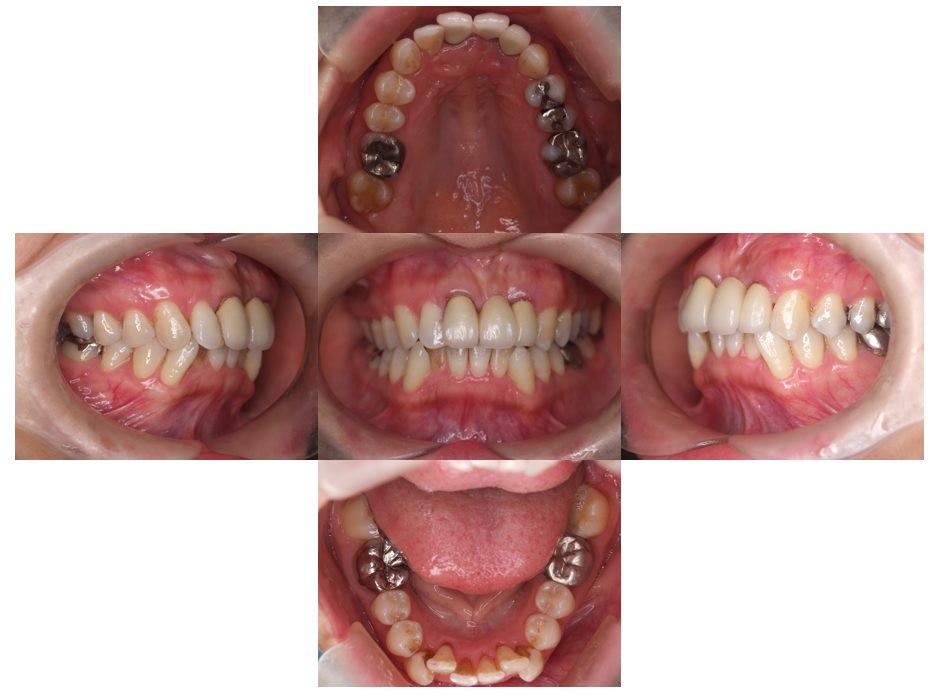

外科矯正治療・インプラント治療の症例紹介(三隅歯科クリニック)

三隅 賢祐(三隅歯科クリニック)

症例詳細

| 主訴 | 20代女性 矯正治療希望。治療途中の歯もあるので治したい。左顎関節が痛い。 |

| 治療内容 | 矯正治療を行いました。 |

| 治療費 | 1,400,000円(税込み) |

| 治療期間 | 3年(矯正治療期間 2年半) |

| 治療回数 | 40回 |

| 想定されたリスク | 顎骨の変形があったので、全身麻酔下による外科処置が必要になり、身体的、精神的負担が増す可能性がありました。 清掃状況によっては矯正中にむし歯が発生するリスクがありました。 |